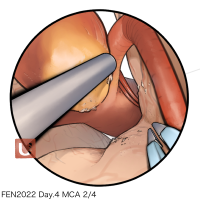

FEN2022シリーズ